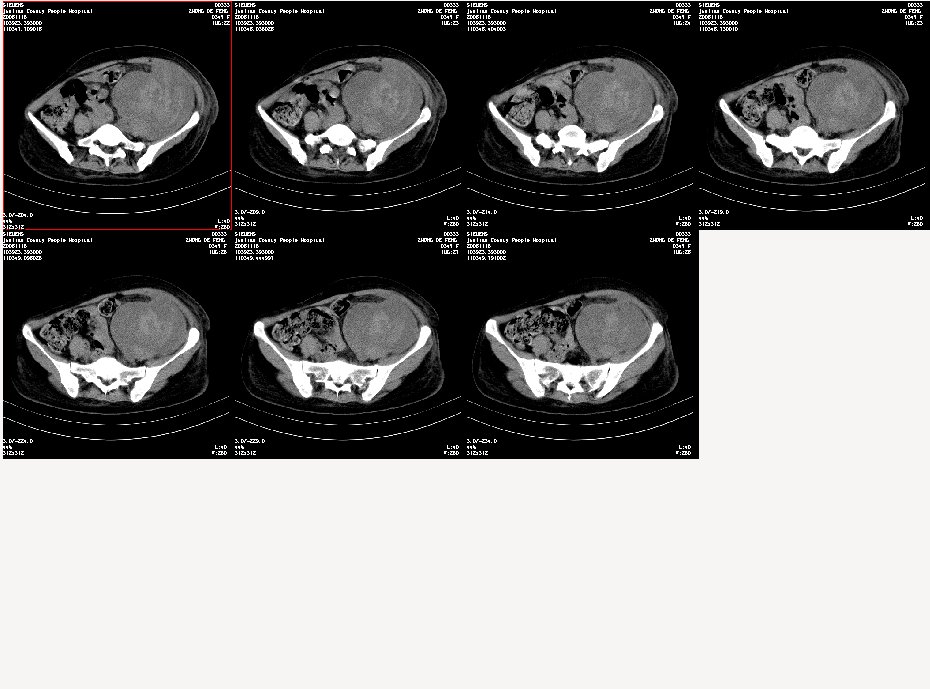

女,34岁,发觉腹部包块1周,查体:腹膨隆,左腹自肋下至髂嵴扪及10x8cm左右包块,触痛明显,固定

病变自脾下至盆腔,范围广泛,左肾显示不清,似向前内侧推移,考虑病变来源于腹膜后;病变边界不清恶性可能性大;建议增强进一步明确。

考虑左侧腹膜后恶性肿瘤侵犯左侧腰大肌及腹主动脉周围。

到三级医院增强结果出来了,是腹主动脉瘤破裂出血,血肿形成。